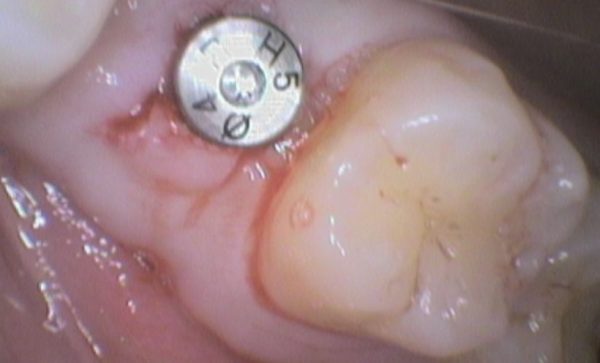

Case 29